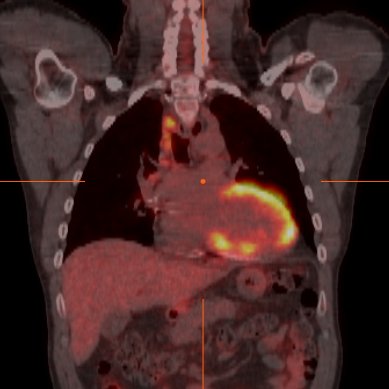

A new @PennCardiology #clinicalcase aimed to: 👉formulate diagnoses of persistent FDG uptake on serial PET imaging 👉understand the mechanistic rationale of alt. causes that may result in persistent FDG uptake https://t.co/ZJ8UQxe534 #Aneurysm #CVImaging @mkvidula @pacoebravo

Diagnostic yield of whole-body 18F-FDG PET/CT in patients with suspected cardiac sarcoidosis

A new @pennmedicine study investigated the effect of immunosuppressive 🩺 therapy & biopsy 💉 status to achieve CTR, PTR or NR on myocardial FDG-PET/CT. Learn more➡️ https://t.co/H5RollrTyg @senthil_selv @mkvidula @leegoldbergmd8 @pacoebravo

Through #cvNuc FDG-PET, a favorable response was more common when using moderate-to-high intensity steroids. After nearly 5 years, biopsy-proven and with preserved systolic function were less likely to experience adverse outcomes. https://t.co/b3AZsOdPTe #JACCIMG #Sarcoidosis